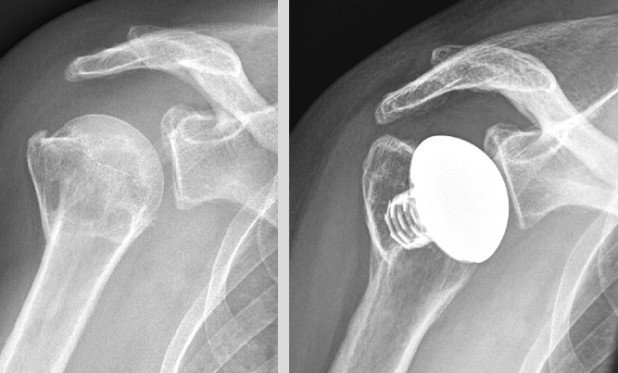

Ist es beim Unfall zu einer erheblichen Verschiebung der Knochenfragmente gekommen, sind die Chancen auf ein gutes Ausheilen und Wiedergewinnen der Schulterfunktion ohne Operation schlecht. Durch den chirurgischen Eingriff werden die einzelnen Knochenteile mittels Schrauben und Platten wieder in die korrekte Stellung und Achse zum restlichen Oberarm gebracht und fixiert. Wenige Tage nach dem Eingriff beginnt die Krankengymnastik damit das Risiko einer Einsteifung minimiert werden kann. Mit zunehmendem Alter verändert sich die Knochenqualität. Der Knochen wird fragiler und die Behandlung von Frakturen schwieriger. In gewissen Fällen kann die sichere Verankerung von Schrauben und Platten nicht mehr erreicht werden. Solchen Patienten ermöglicht das Einsetzen eines Kunstgelenks eine gute Option auf eine erfolgreiche Behandlung.

Knochenbrüche der Oberarmkugel betreffen direkt das Schultergelenk. Daher besteht im mittel- und langfristigen Verlauf ein erhöhtes Risiko für die Entwicklung einer Schultergelenksabnützung (Arthrose). Da im Rahmen des ursprünglichen Unfalles auch die Blutversorgung der Knochenfragmente geschädigt werden kann, ist das Absterben des Knochens (Nekrose) eine weitere mögliche Komplikation. Auch in diesem Fall kann mittels Kunstgelenkversorgung eine gute Schmerzbefreiung und Wiedergewinnung der Beweglichkeit und Schulterfunktion erzielt werden.